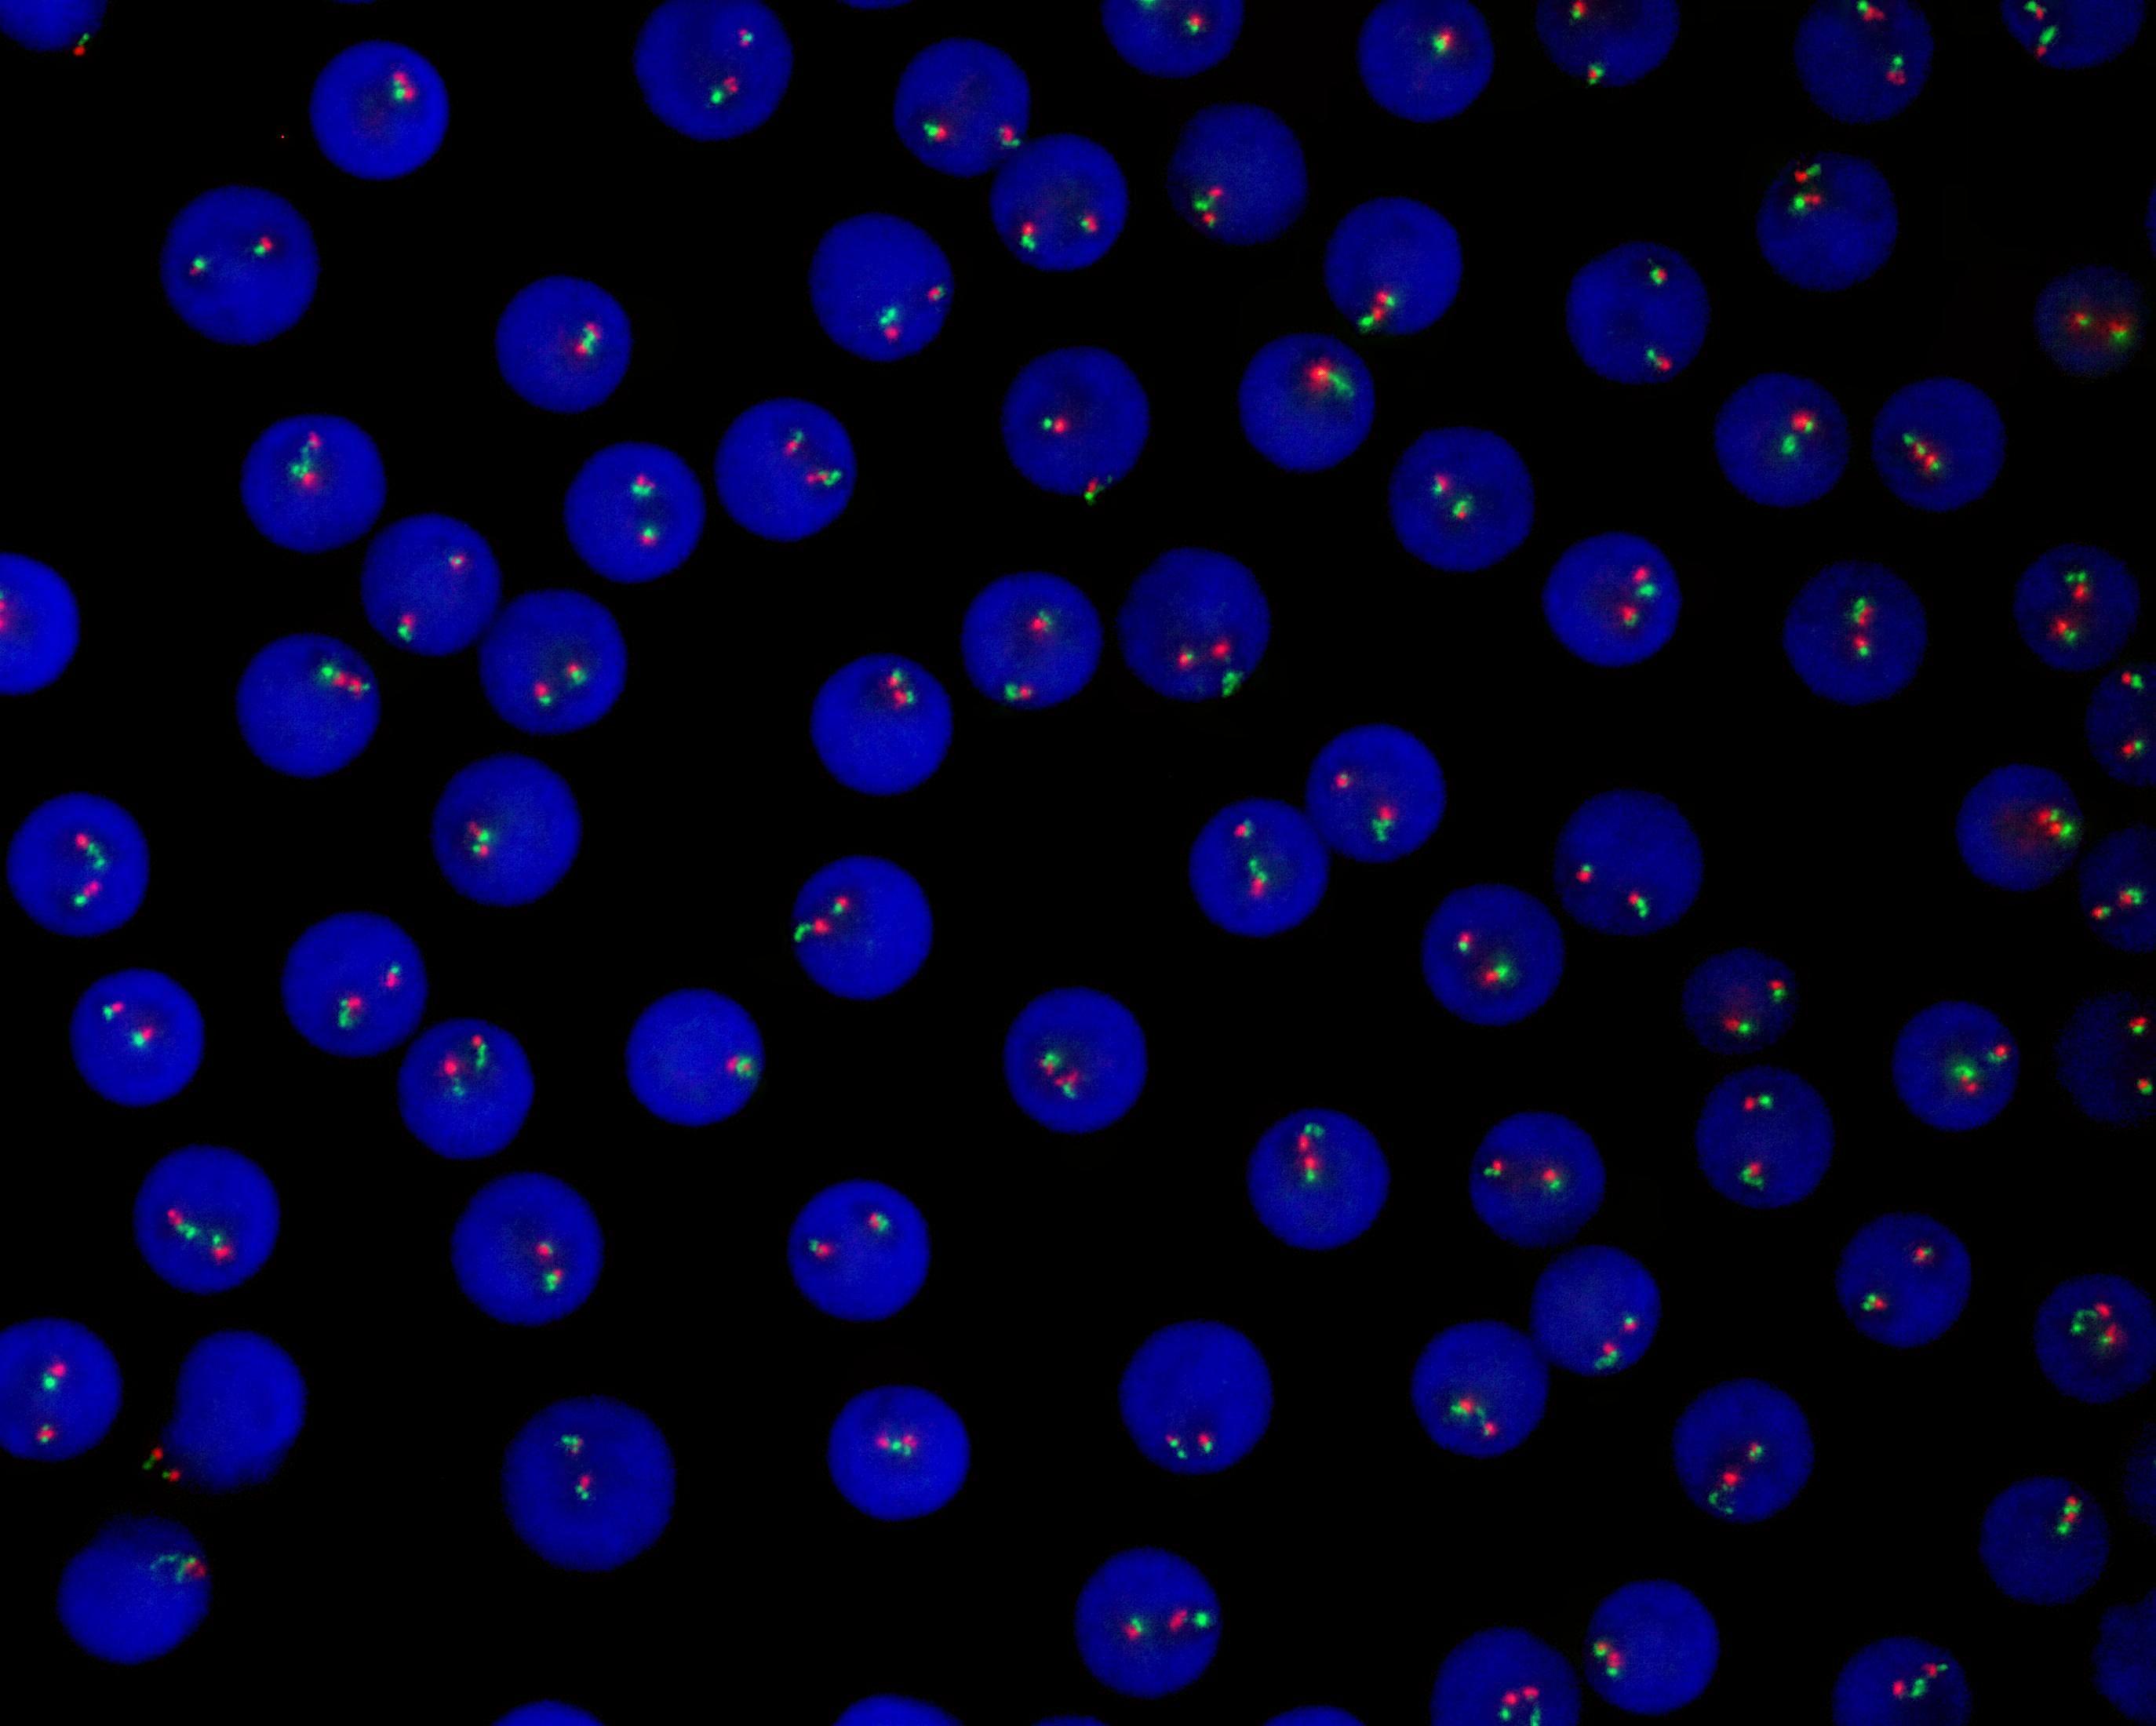

E2A gene break apart probe reagent

E2A dual color probe

E2A gene 5’ end labeled as orange, with a length of 210 kb; E2A gene 3’ end labeled as green, with a length of 390 kb.